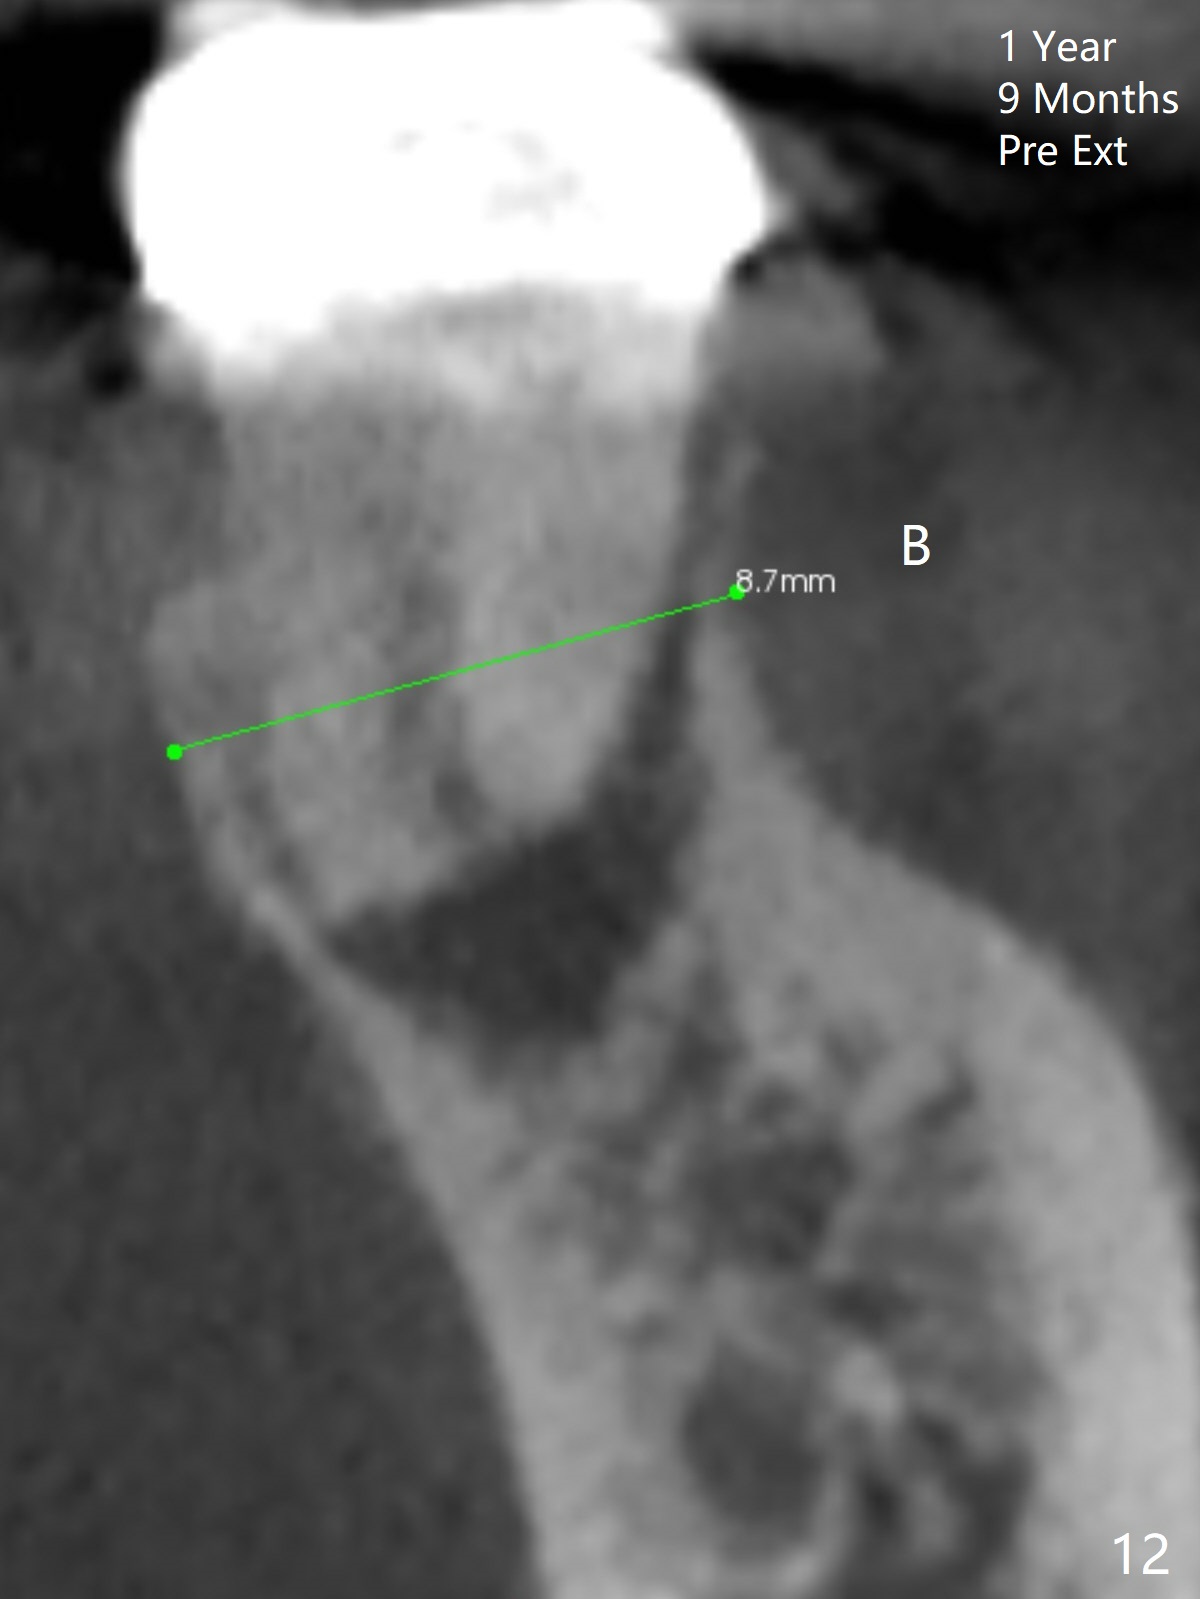

After making a 10 mm incision at the site of #19, #15c blade is used as an osteotome to start bone expansion, followed by Magic Split and Magic Expander (ME, 3 mm in diameter).  The depth is approximately the bottom of the mesial socket.  The osteotomy beyond the socket has to be done with 1.6 mm pilot drill (Fig.1) in combination of ME.  Following ME 4.3 mm and Magic Drill (MD) 3.8 mm for 15 mm (gingival level), a 4.5x11 mm dummy implant is placed with 50 Ncm (Fig.3); the implant looks narrow for the edentulous space.  After ME 4.8, MD 4.3 for 13 mm and Final Drill for 15 mm, a 5x11 mm IBS is inserted with >50 Ncm (Fig.3).  With 2 more turns of the implant, a 6.5x4(2) mm abutment is placed (Fig.4).  Periodontal dressing is applied around the abutment for additional retention.  A provisional is fabricated 3 weeks postop.  The provisional and abutment are loose 4 months postop (Fig.5).  After retightening the abutment, impression is taken for final restoration.  There is no bone loss 1 year 3 months post cementation (Fig.6).  After use of #100 file (Fig.7), the canal is debrided with #140 file with 1.5 mm shorter in working length with placement of Calcium Hydroxide paste.  Pain gets worse post RCT retreatment. There is limited native bone for primary stability when an immediate implant is placed (red dashed line: the superior border of the Inferior Alveolar Canal).  Prepare IS regular and extra wide kits and tissue-level implants (>5 mm).  Socket preservation may be done instead.  If the socket is large and the vein is not so small, prepare PRF.  In fact blood drawing fails.  When the tooth is extracted, it is sensitive to remove granulation tissue.  Socket preservation is done with Vanilla graft at #18 (Fig.8); there is ~3.5 mm bone between the bottom of the single socket and the Inferior Alveolar Canal (red dashed line).  The socket at #18 seems to have healed 4 months post extraction (Fig.19), but the bone height appears to have been reduced (compare Fig.10,11).  The buccolingual width is also decreased (Fig.12,13).  A 4.5 or 5.0x10 mm implant is appropriate for the site (Fig.14).  There is no bone loss at #19 (which may be associated with the bone expansion) 1.5 years post cementation (Fig.15).  Therefore the osteotomy at #18 will be assisted with bone expanders after 2.2 mm drill.